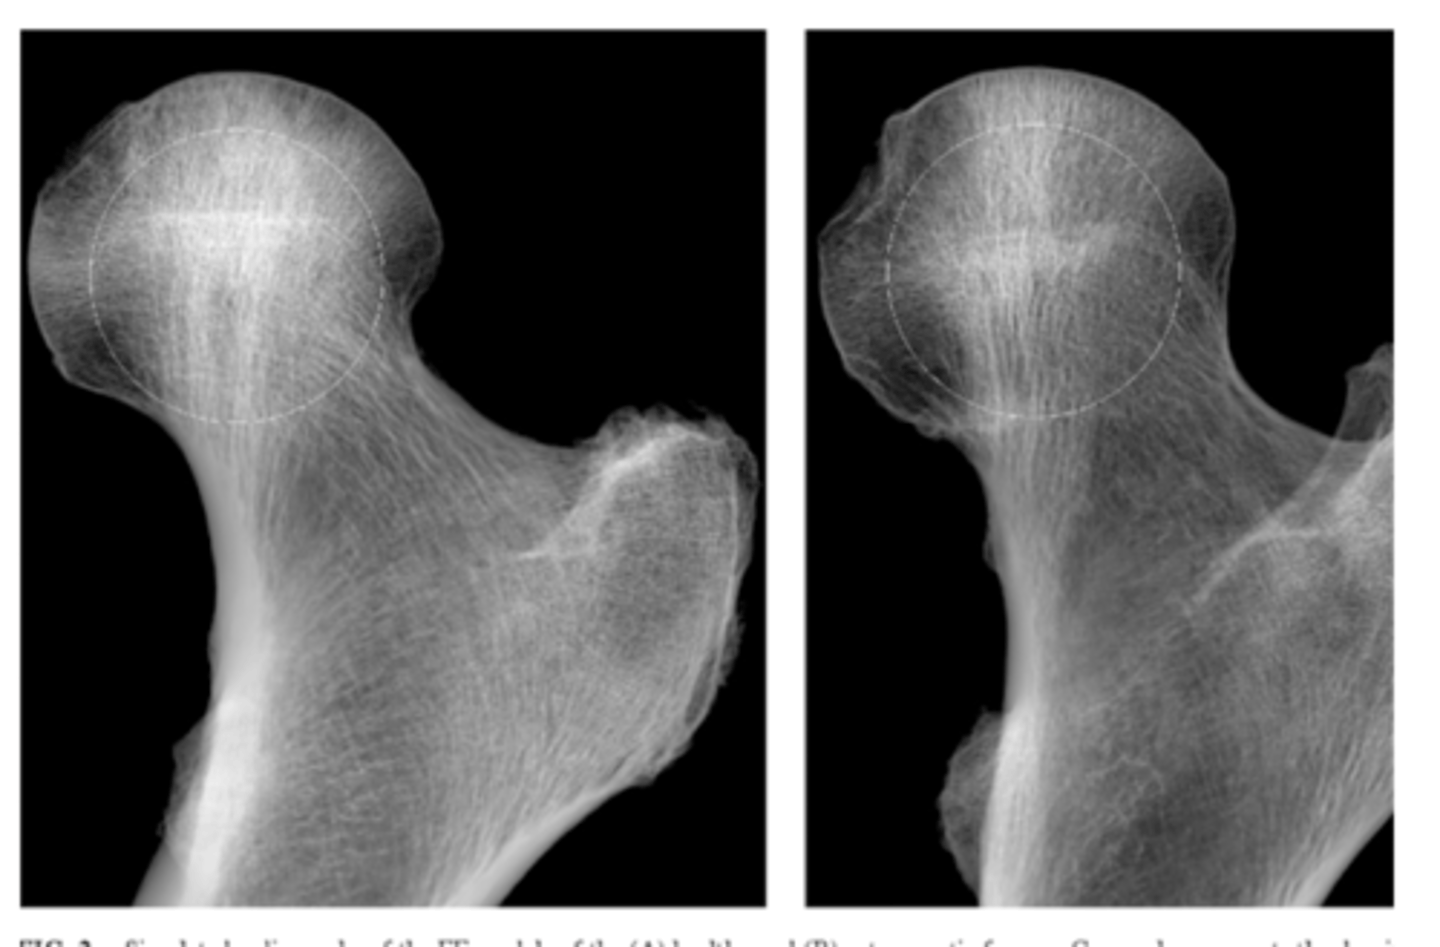

List the 3x components of (B) bone density when interpreting a plain film radiograph

1. General bone density

2. Textural abnormalities - trabeculae

3. Local density changes - sclerosis

Explain why evaluating (B) bone density: textural abnormalities - trabeculae is clinically relevant

A decrease in bone density may indicate osteoporosis

**be careful in distinguishing osteoporosis from what normally looks radiolucent (i.e., it is normal for trabecular bone to be less dense than cortical bone)**